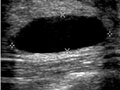

Abnormal: | - A fluid-filled sac (cyst) is present. A fluid-filled lump that is evenly

shaped and has no particles floating in it is likely to be a simple cyst. This

may not need more tests. See an ultrasound image of a

simple breast cyst.